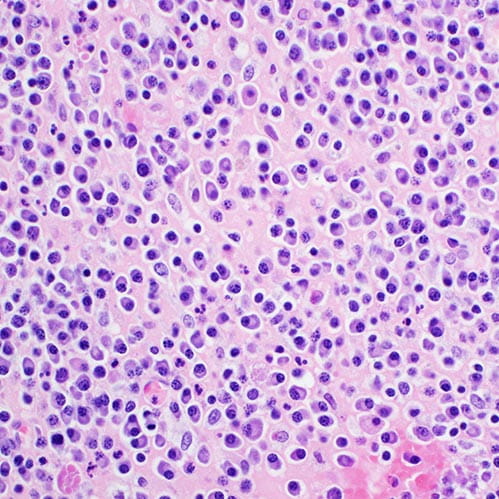

H&E stain, light microscopy, multiple myeloma

Multiple Myeloma

plasma cells